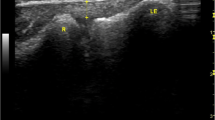

All ultrasounds were bilateral according to a standardized protocol using the Aixplorer machine (SuperSonic Imagine, Aix-En-Provence, France) equipped with a 12-MHz superficial linear transducer. Patients were placed in a prone position, with legs extended. The examination began with grayscale B mode and power Doppler ultrasound to eliminate any signs of tendinopathy. The width (mm) and thickness (mm) of each tendon were measured with axial (i.e., perpendicular to the direction of the fibers) grayscale ultrasound 5 cm from the end of the tendon. The cross-sectional area (mm2) of each tendon was calculated using the following formula: cross-sectional area = π × width/2 × thickness/2. Measurements in elastographic mode were made successively for four passively mobilized ankle positions: position no. 1: maximal plantar flexion; position no. 2: 45° plantar flexion; position no. 3: 0° flexion; position no. 4: 45° dorsiflexion or maximal dorsiflexion for patients who did not sustain 45° dorsiflexion (Fig. 1). The mean shear wave velocity (Vmean, m.s−1) was measured in elastographic mode (SWE) by placing a region of interest (ROI) with the following requirements: constant round size (3 mm in diameter) situated in the center of the tendon 5 cm from its end, both in sagittal (i.e., parallel to the direction of the fibers) and in axial SWE (Fig. 2). Young’s modulus Emean (kPa) was calculated from Emean = 3 ρVmean 2[13] where density ρ is assumed to be constant (1,000 kg.m−3), under the assumption of a purely elastic model. Standard deviation of the ROI was used as an estimate of the quality of the measurement: standard deviation of shear wave velocity (VSD) and the standard deviation of Young’s modulus (ESD) within the ROI were also measured. The relative anisotropy coefficient (A) was calculated using the following formula: A = (sagittal Vmean – axial Vmean)/sagittal Vmean.

Calcaneal tendon was examined at 5 cm from the end of the tendon consecutively for four degrees of ankle flexion. Position no. 1: maximal plantar flexion; position no. 2: 45° plantar flexion; position no. 3: 0° flexion; position no. 4: 45° dorsiflexion. As it may have increased tissue stiffness, pre-compression was avoided by interposition of a gel pad between the probe and the skin. The position was maintained and controlled by fastening feet on an articulated board

Data of the right and left tendons were grouped together so that 160 tendons were studied. In the axial ultrasound, the thickness of the calcaneal tendon was 4.4 ± 0.6 mm, the width was 15.1 ± 1.9 mm, and the cross-sectional area was 53.1 ± 11.7 mm2. The results of the elastographic analysis are shown in Table 1. In the axial SWE, there was a significant increase in the Vmean and Emean between positions no. 1 and no. 2 (p < 0.001), and between no. 3 and no. 4 (p < 0.001), but there was no significant difference in these variables between positions no. 2 and no. 3 (Vmean p = 0.62 and Emean p = 0.7, respectively). In the sagittal SWE, there was a significant increase in Vmean and Emean between positions no. 1 and no. 2, no. 2 and no. 3, and between no. 3 and no. 4 (p < 0.001). The relative anisotropy ratio A was 0.24 ± 0.16 in position no. 1. It increased significantly between positions no. 1 and no. 2 (p < 0.001), and between positions no. 2 and no. 3 (p < 0.001). However, there was a statistically significant drop between positions no. 3 and no. 4 (p < 0.001). In the sagittal SWE, there was a significant increase in VSD and ESD between position no. 1 and no. 2 (p < 0.001), and between no. 2 and no. 3 (p < 0.001), but there was a significant reduction in these two variables between positions no. 3 and no. 4 (p < 0.001). In the axial SWE, there was no significant difference in VSD and ESD between positions no. 1 and no. 2 (VSD p = 0.1 and ESD p = 0.6), but they both increased from positions no. 2 to no. 3 and from no. 3 to no. 4 (p < 0.001).

Our results also confirm the increase in Emean, Vmean, and A when the calcaneal tendon was stretched, regardless of whether the measurements were made in the sagittal SWE (Fig. 3a) or in the axial SWE (Fig. 3b). Arda [19] did not carry out a dynamic study. In vivo, the princeps study was carried out on a smaller number of volunteers (n = 30), with only three different ankle positions [18]. The upper limit for measuring Young’s modulus (600 kPa) was lower than that of our device (800 kPa). Therefore, the values published in the sagittal SWE at 0° and in complete dorsiflexion were under-estimated [18]. These values are probably still under-estimated because the upper limit (800 kPa) is often reached for these two positions in the sagittal SWE. Consequently, it is unrealistic to try to reproduce usual movement and position with extra-weight (or supporting the weight of the patient) because the current limit of the device (800 kPa; 16 m.s−1) would also be exceeded.